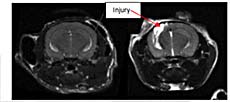

Understanding location and severity of a brain lesion and its response to therapy is one application where MRI is advantageous.

Here we use MRI to study development of the traumatic injured area over time.